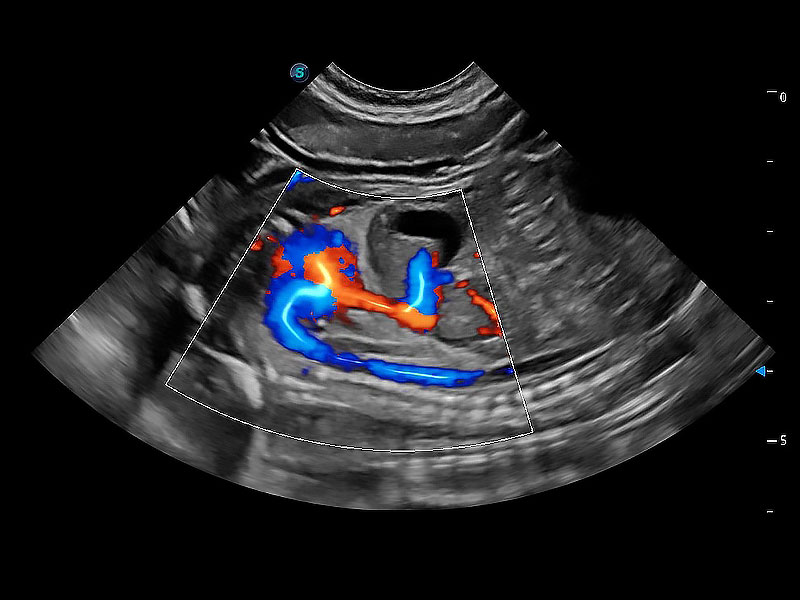

高性能和先进的临床应用工具可以为动物医生提供临床信心。ProPet 80 搭载了先进的腹部和浅表应用工具,帮助医生在日常临床实践中发挥前所未有的作用。

极大提升超低速微细血流的检出能力,同时更精准地滤除软组织和超声信号,为兽用医生提供以往无法通过常规血流获得的疾病诊断信息。

在传统二维血流成像的基础上,呈现血流的立体感,具有动感的生命力之美。即便是微小的血管也能轻松应对,提高了血流的视觉敏感性。